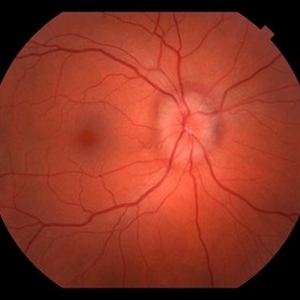

AVM 2

Atrophy of lesion with observation.

Photographer: Wayne A Ladlee Jr

Imaging device: Cirrus

Condition/keywords: aquired vitelliform maculopathy